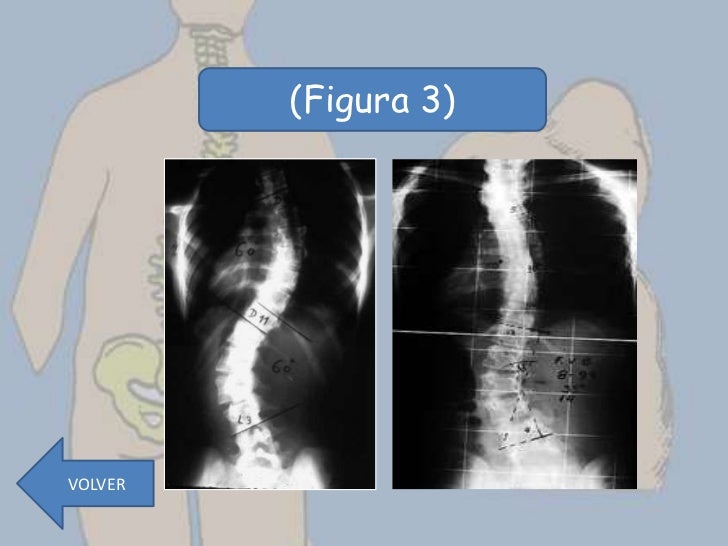

Discusión Figura representativa de 3 pacientes con escoliosis idiopática grave actualizar